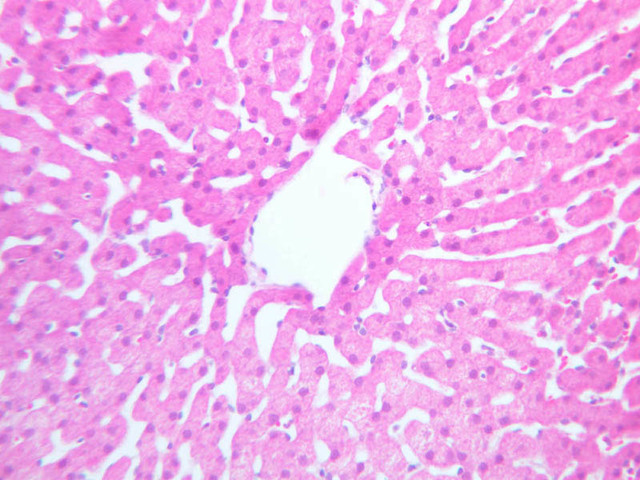

Examine the H&E-stained sections of liver (slides B-29 [10x, 20x, 40x-labeled] [2.5x-labeled, 10x, 20x, 40x] [10x-labeled, 20x, 40x-labeled] and B-30 [2.5x, 10x-labeled, 20x]). At low power, identify the connective tissue capsule (Glisson’s capsule), central veins and portal triads (portal canals). Note that the cells of the liver parenchyma (hepatocytes) appear as cords--more accurately, plates--of cells that radiate out from the central veins and partially enclose blood spaces known as hepatic sinusoids. Note that the plates of hepatocytes appear to branch and fuse and that, as a rule, they are only one or two cells thick. Do you see any binucleate hepatocytes?

Using the 10X (B-29, B-30)and 40X (B-29) objectives, examine several portal triads, noting the variable number of profiles of hepatic artery, portal vein and bile duct that comprise the portal triad. Near the boundary between adjacent lobules, try to find some of the small elements of the bile duct system known as canals of Hering.

Using the high dry objective, study the lining of the central vein and hepatic sinusoids (B-29). In some places the hepatocytes are exposed directly to the sinusoidal lumen, but, as a rule, there is a basal lamina which supports a discontinuous mosaic of endothelial cells and specialized phagocytic cells known as Kupffer cells. Find examples of Kupffer cells and endothelial cell nuclei. Note that in some places you may see a narrow space (the space of Disse) between hepatocytes and the basement membrane underlying endothelial and Kupffer cells. Using the oil immersion (100X) objective, look very carefully along the boundaries between adjacent hepatocytes to see if you can find a bile canaliculus--the most delicate portion of the bile duct system--the walls of which are formed by the plasma membranes of adjacent hepatocytes.